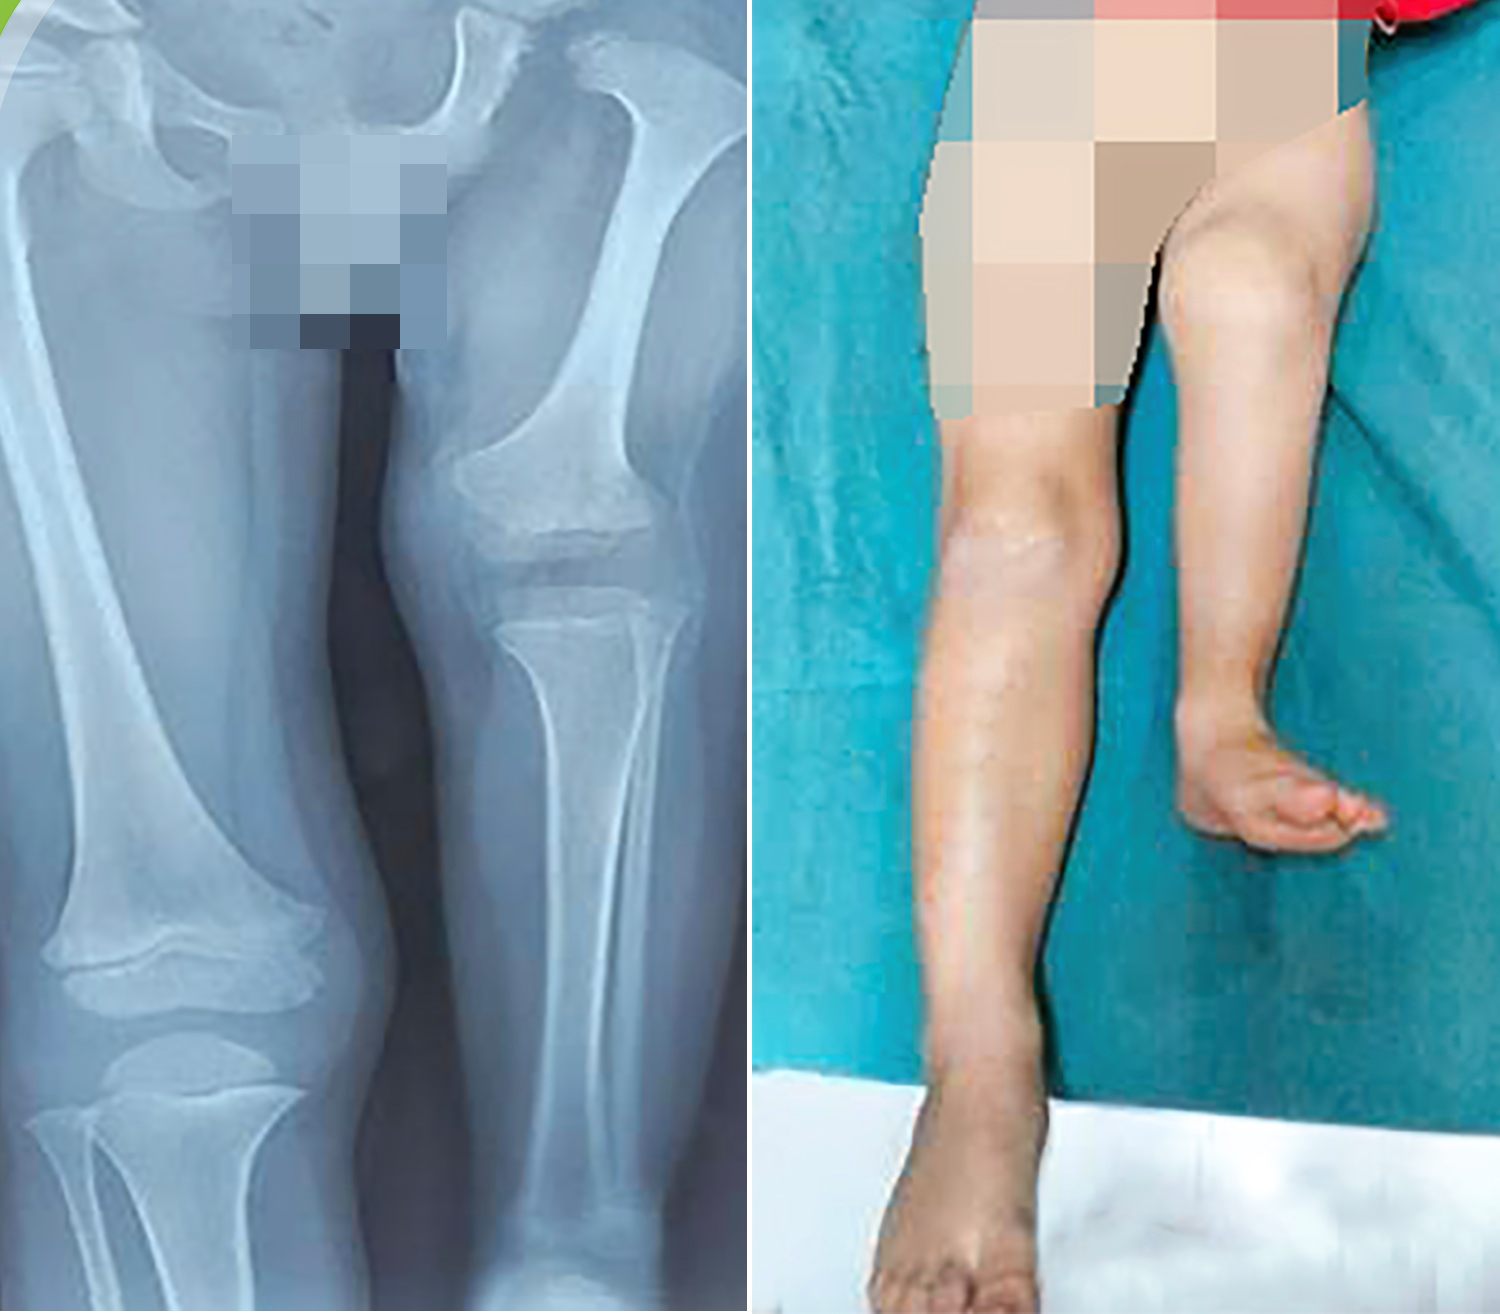

At the time of admission, the left femur of the patient only reached nearly half of its length compared to the healthy side. The knee joints are in a rigid folded position, unable to be fully extended. When placing the two legs parallel, the left foot is only equal to the middle of the right calf, causing a serious difference in the length of the limbs and significantly affecting daily life.

After a thorough professional consultation process at the end of 2025, doctors in the Department of Orthopedics agreed to prescribe Rotationplasty surgery for the patient. This is a special lower limb regeneration technique, in which the diseased thigh and knee joints are removed, the calf is rotated 180 degrees so that the ankle joints play the function of the knee joints. When combined with prosthetics, the ankle joints can perform physiological flexion and extension movements, helping children walk naturally and more effectively than traditional thigh amputation methods.